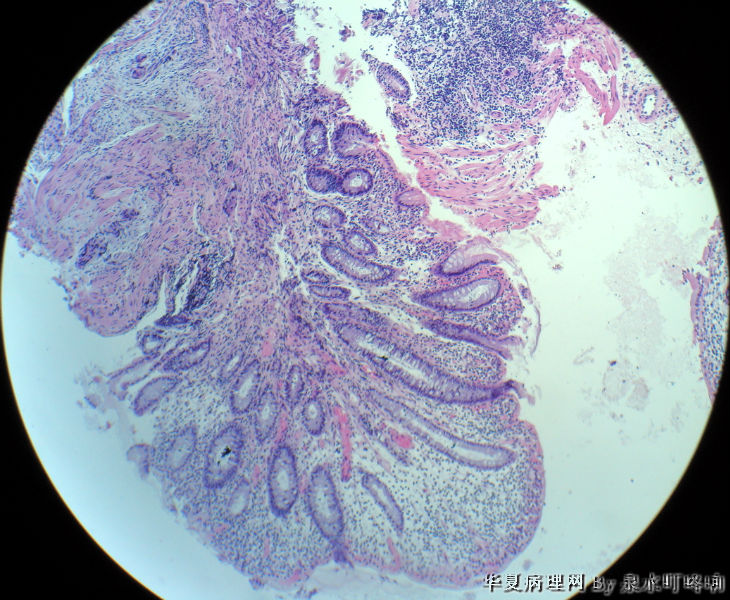

直肠活检

• 直肠活检图2

图2

女,49岁,大便变细2年,结肠镜示距肛门5厘米可见溃疡形成,弥漫肠管全周。

腺癌

纤维组织中可见异型腺体浸润,诊断腺癌。

可见异型腺体,疑为直肠腺癌

分化较好的腺癌。